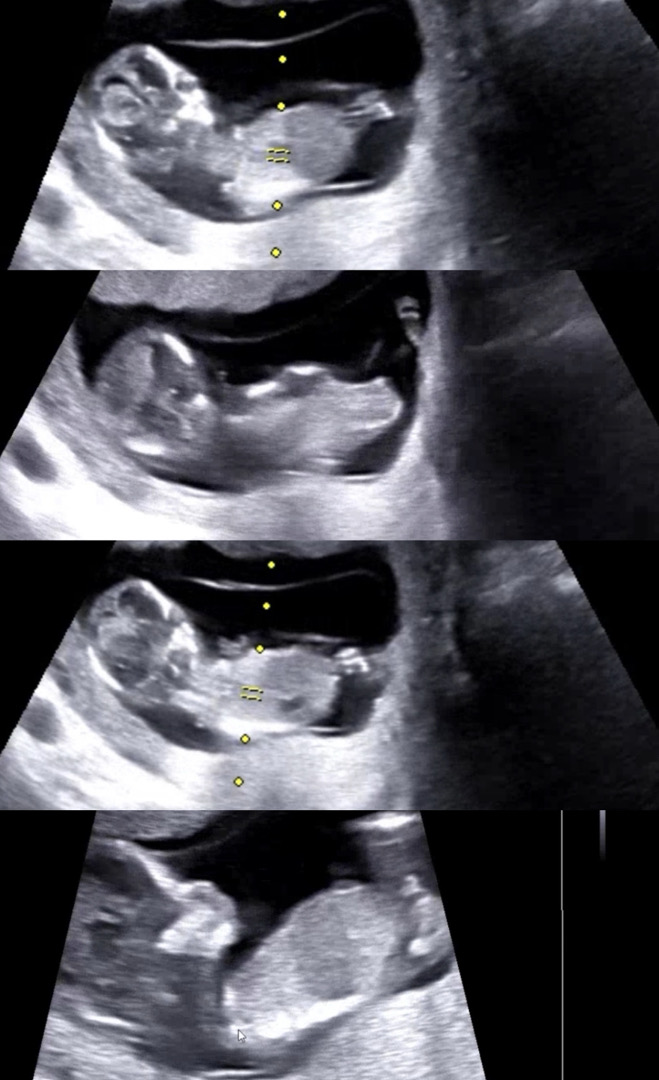

12주6일차 ㅜㅠ 성별한번만 봐주세요!

영상에서도 각도가 애매해서 도저히 모르겠더라구요ㅠㅠㅠ 고수님들 한번만 봐주세요